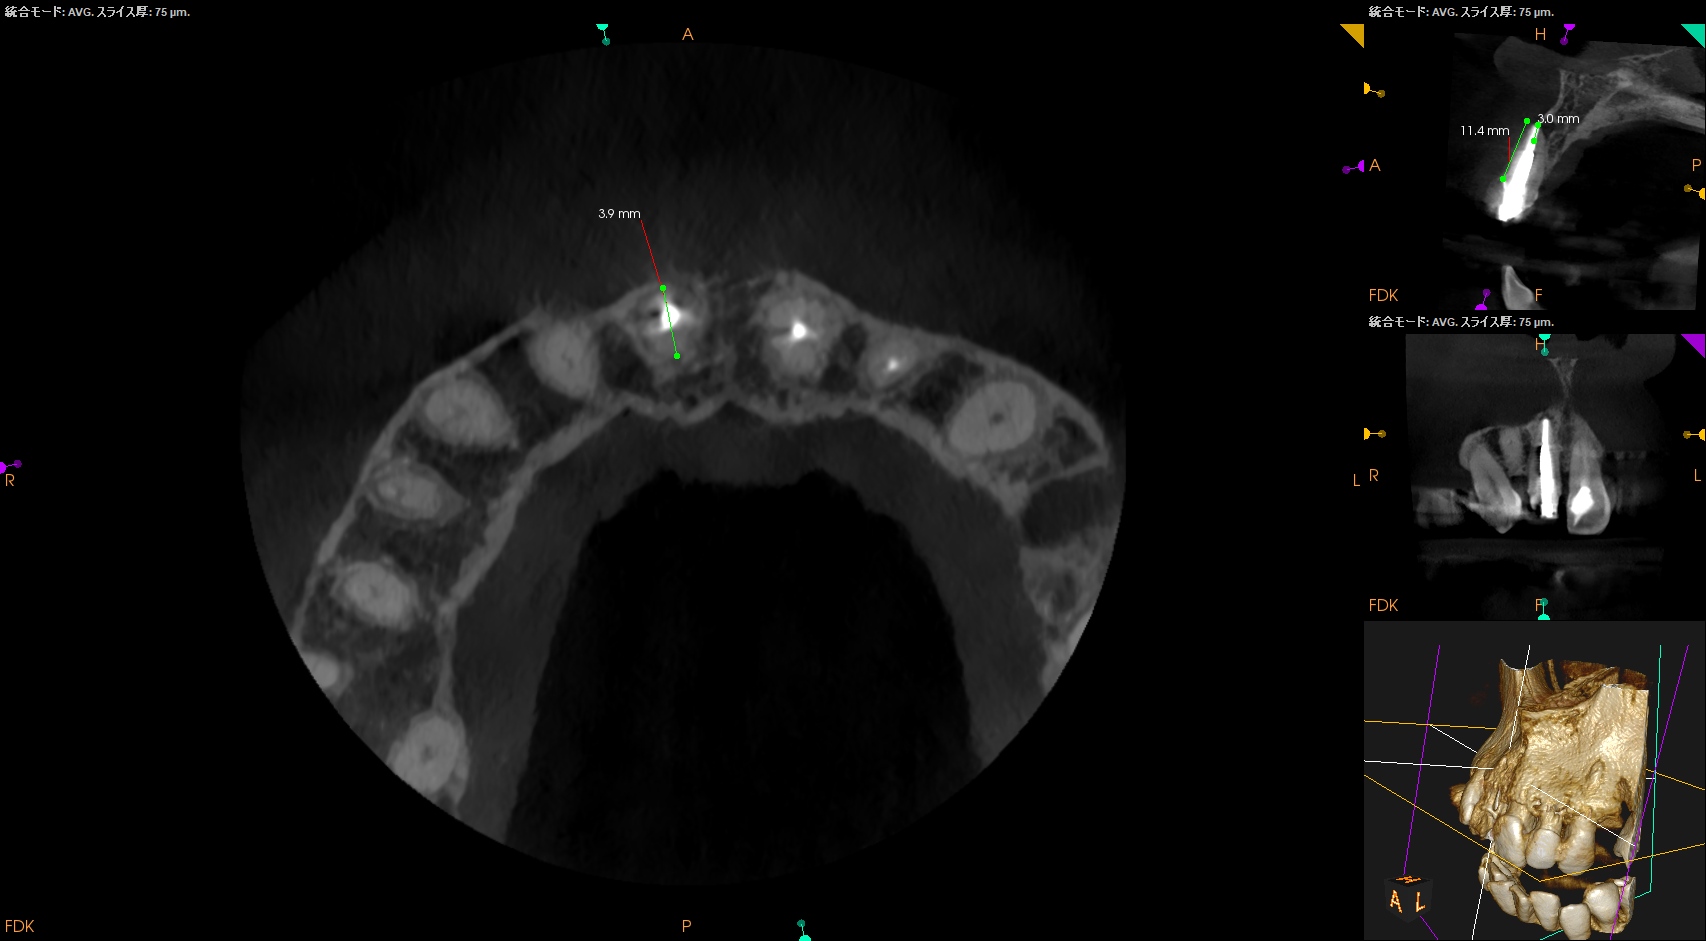

CBCT(2025.1.31)

#8

ということは患歯は#8であり、以上の様子からApicoectomyが適応症だ。

となれば、どう行うか?だが、

クラウンのマージン部から11.5mm下方に#8のApexはあり、

そこを3mm切ろうと思えば、

3.9mmの幅の切削が必要だ。

これは難しくないと考える。

#8の頬側には健全な皮質骨があることから、Submarginal Flapの適応症である。